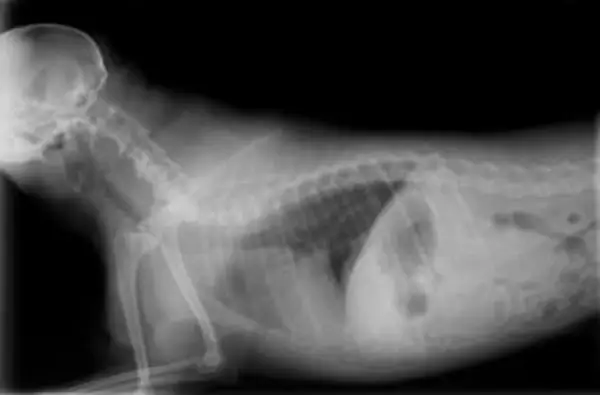

Twój weterynarz może zdiagnozować zapalenie płuc za pomocą połączenia badania fizykalnego (słuchanie płuc) i prześwietlenia klatki piersiowej. Badania krwi mogą być pomocne w znalezieniu innych czynników, które mogą przyczynić się do przyczyn leżących u podstaw. Czasami twój weterynarz może zlecić specjalny test, aby pobrać próbkę z płuc, aby określić, jaki rodzaj bakterii powoduje infekcję i który antybiotyk będzie działał najlepiej. W przypadku psów z aspiracyjnym zapaleniem płuc weterynarz może potrzebować dodatkowych testów, aby zdiagnozować przyczynę aspiracji.

Twój weterynarz będzie podejrzewał zapaść tchawicy, jeśli twój pies jest małej rasy i ma klasyczny kaszel gęsi. W większości przypadków diagnoza może zostać potwierdzona przez lekarza weterynarii, wykonując prześwietlenie szyi i klatki piersiowej. W przypadku niektórych psów mogą być potrzebne inne testy, takie jak fluoroskopia lub endoskopia.

Diagnoza przewlekłego zapalenia oskrzeli

Twój lekarz weterynarii wstępnie zdiagnozuje przewlekłe zapalenie oskrzeli słuchając płuc psa i robiąc zdjęcia rentgenowskie klatki piersiowej. Te wstępne testy pomogą wykluczyć inne rodzaje chorób płuc, ale konkretna diagnoza przewlekłego zapalenia oskrzeli wymaga płukania oskrzelowo-pęcherzykowego w celu pobrania próbki z płuc psa. Laboratorium oceni następnie próbkę pod mikroskopem, aby określić, jakie typy komórek są obecne, aby postawić diagnozę.

Jeśli uważasz, że Twój pies może mieć zastoinową niewydolność serca, potrzebna jest natychmiastowa wizyta u weterynarza. Niektóre zwierzęta z ciężką niewydolnością oddechową będą wymagały tlenu i leków, zanim będą mogły zostać wykonane jakiekolwiek testy. Lekarz weterynarii może postawić wstępną diagnozę niewydolności serca na podstawie objawów, wieku i rasy psa oraz nasłuchując w płucach dźwięków związanych z gromadzeniem się płynów lub szmerem serca. Rozpoznanie zastoinowej niewydolności serca można zwykle postawić na podstawie badania fizykalnego i prześwietlenia klatki piersiowej. W przypadku niektórych psów może być konieczne wykonanie echokardiogramu (USG serca), ale w wielu przypadkach nie można tego wykonać natychmiast.

W przypadku bardziej przewlekłego ciała obcego weterynarz może czasami postawić diagnozę za pomocą prześwietlenia szyi i klatki piersiowej. W niektórych przypadkach weterynarz może chcieć wykonać tomografię komputerową, fluoroskopię lub bronchoskopię.

Rak płuc może naśladować wiele innych chorób, które powodują kaszel u psów. Twój weterynarz może zwykle postawić wstępną diagnozę za pomocą prześwietlenia klatki piersiowej, ale potwierdzenie może wymagać wielu dodatkowych testów lub biopsji.

Diagnostyka i leczenie blastomykozy